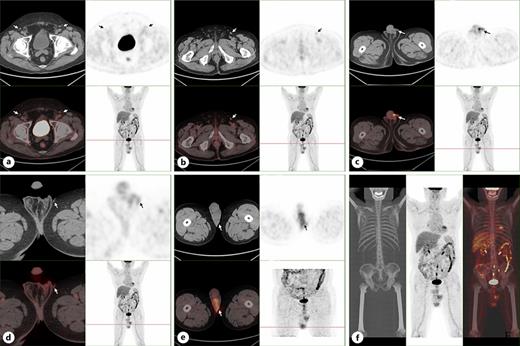

A 74-year-old male patient was admitted to our department due to experiencing patchy erythema and pruritus in the perineal area for over 5 years and the lesions progressively expanding with skin ulceration over the past 3 months. Five years ago, the patient initially noticed the patchy erythema on the scrota skin, which was covered with a small amount of white scales and accompanied by pruritus. The patient initially used acyclovir ointment to treat it by himself. After the pruritus symptoms relieved, the patient did not seek further medical care. However, 3 months ago, the patient observed that the lesions of scrota skin had gradually expanded to the pubic mound and penis, so he was admitted to our hospital for treatment. The patient had a medical history of hypertension for more than 14 years and diabetes for over 3 years. Upon physical examination, no abnormalities were detected in all systematic examinations and no enlargement of the lymph nodes was found in the bilateral inguinal region. Flake erythema of about 12.5 cm × 10.0 cm could be seen in the scrotum, penis, and pubic mound, with a few white scales overlying it. Skin ulceration and dark red blood scabs could be observed in the lesion. There were clear boundaries between the lesion and surrounding tissue (Fig. 1). There were no obvious abnormalities in blood routine, urine routine, liver and kidney function, and other laboratory examination tests. PET/CT results showed that the skin of bilateral scrotum was slightly thickened with increased metabolism, which was consistent with the appearance of malignant tumor, and the density and metabolism of the left testis were increased, which were considered as tumor invasion (Fig. 2). In histopathological examination, many scattered vacuolated Paget cells were observed in the epidermal layer, which had large cell bodies, abundant and light-stained cytoplasm, large and dark-stained nuclei. Besides, abnormal mitotic images were observed in Paget cells (Fig. 3). Immunohistochemical results showed GCDFP-15(focal +), CK7(+), CK20(+), EMA(+), MUC5AC(+), CEA(+), GATA3(+), CK5/6(−), P40(−), P63(−), Ber-EP4(−), KI-67(+30%), P53(+5%), CD56(−), Syn(−), AR(+) (Fig. 4). The pathological diagnosis was Paget’s disease of the scrotum and penis. Under general anesthesia, a wide local excision (WLE) of the lesion, bilateral orchiectomy, and adnexectomy were performed on the patient. The 2 cm outside the skin lesion was used as the initial surgical margin, and free skin flap transplantation was used to repair the surgical wound. The patient recovered well and was discharged 1 week after surgery.